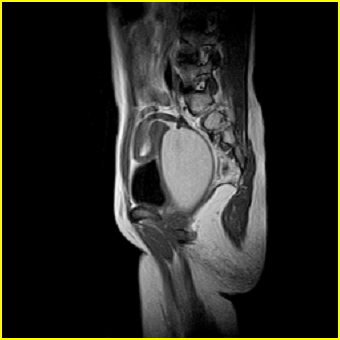

女、15岁、下腹疼痛2天,排尿困难1天。查体:处女膜闭锁,距处女膜约4至5cm处扪及一约5cm直径的圆形包块,张力较高,触痛明显、欠活动。b超提示子宫增大伴宫内增强回声团。

影像意见:子宫直肠陷凹积血。

更正影像意见:阴道积血。

处女膜闭锁,阴道积血

处女膜闭锁,阴道积血,子宫积血.

先天性处女膜闭锁,伴阴道积血,不除外先天性阴道粘液囊肿形成。

阴道积血,子宫积血.

子宫及阴道积血。

处女膜闭锁,伴子宫及阴道积血.